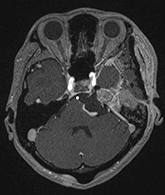

症例2) 31歳女性、頭蓋底部巨大髄膜腫、外科手術+放射線治療

<画像所見>

腫瘍はほとんど消失している。術後患者様は右眼瞼下垂、複視(動眼神経麻痺)生じたが、自宅退院された。